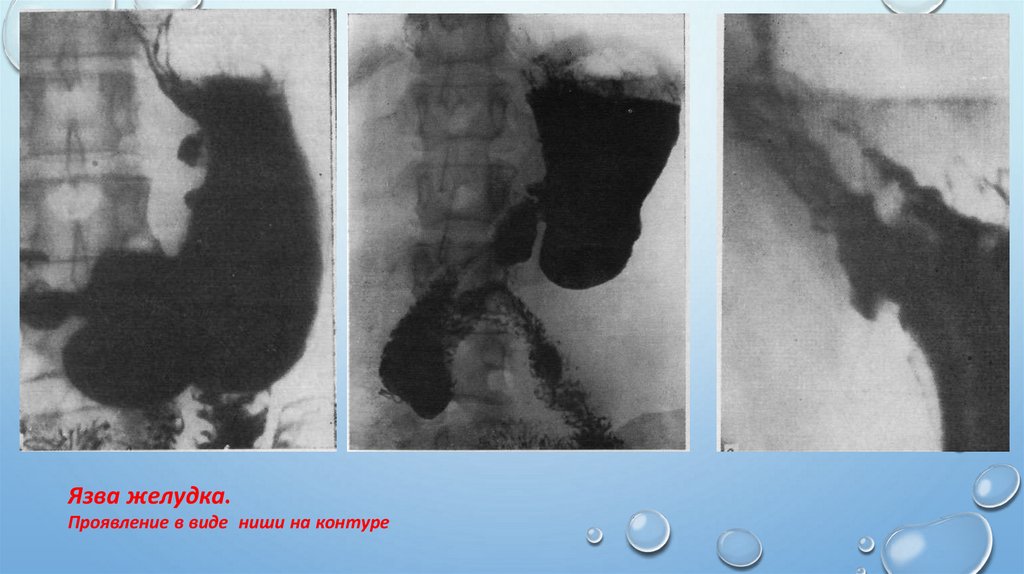

Основные симптомы важнейших заболеваний кишечника.

Язва желудка.

Проявление в виде ниши на контуре

50.

Язва желудка

Проявление в виде ниши на рельефе =депо бария

Депо бария. Воспалительный

вал вокруг язвы. Конвергенция

складок к язве.

Ниша на рельефе с

конвергенцией

складок к язве. Двойное

контрастирование

(пневморельеф).

Больной

лежит на животе.

51. Локальное расширение и изменения рельефа желудка - Язвенная болезнь.

Ниша на контуре

Ниша на рельефе